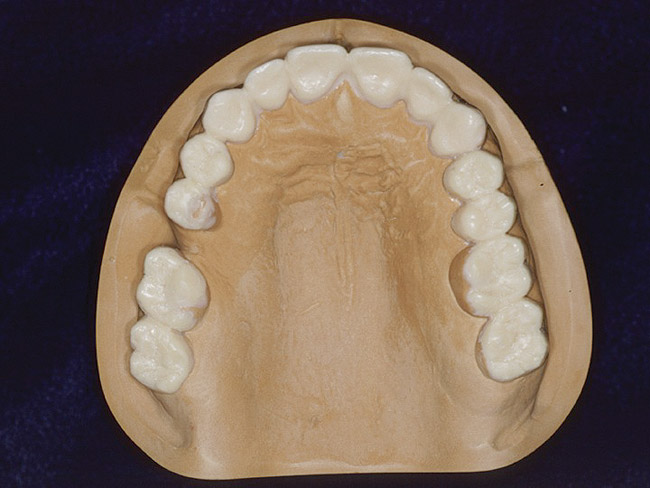

Figure 16 THROUGH 19. Complete full mouth wax-ups after final determination of 3D VDO.

Figure 16

Figure 17

Figure 18

Diagnostic Wax-Ups and Set-Ups

One of the most valuable ways to assess vertical dimension is to use wax-ups to create mock overlays to test clear speech for an appropriate vertical dimension (Figure 14 and Figure 15). When anterior diagnostic acrylic or composite overlays (or “mock veneers”) are used to test fricatives, clear [f] and [v] sounds are made when the incisal edges of the maxillary teeth touch just inside the wet/dry border of the lower lip. Clear sibilant [s] and [z] sounds occur when the lower and upper incisal edges almost touch, allowing a clear hissing sound to be made. Improved esthetics is also dramatic. Once these sounds are clear, the closest speaking space can be created with diagnostic wax-ups in the posterior space (Figure 16 through Figure 19). The final result will depend on successful development of 3D VDO comparing a number of methodologies.